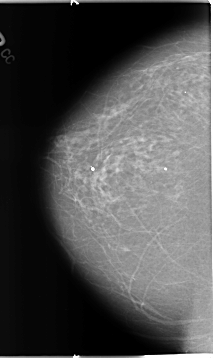

RIGHT_CC LINES 4648 PIXELS_PER_LINE 2760 BITS_PER_PIXEL 12 RESOLUTION 50 NON_OVERLAY